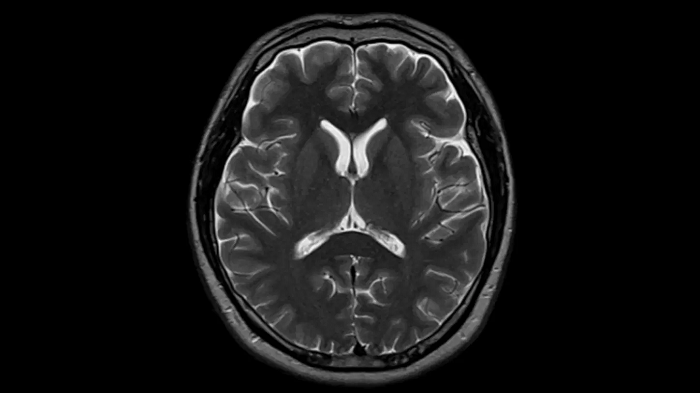

Head

T2 TSE with Deep Resolve

To produce high-resolution images, Deep Resolve, the Al-powered image reconstruction technology gets benefits from intelligent denoising and neural networks.

Deep Resolve Gain & Sharp

0.4 x 0.4 x 5.0 mm2

TA 2:50 min

MAC-ID: 7aaaa0195. Image Credit: Siemens Healthineers